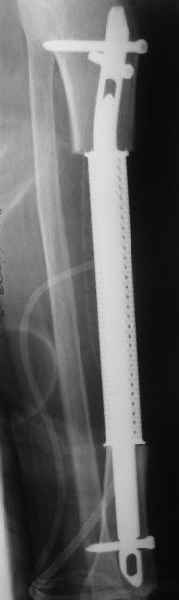

Недавно на нашей ежемесячной Morbidity&Mortality

conference мы разбирали похожий случай, ложный сустав большеберцовой кости после резекции опухоли.

К нашему онкологу-ортопеду обратился больной с жалобами на боли в голени, из рассказа - год назад была сделана биопсия большеберцовой кости, но название заболевания "не запомнил”.

Оперирован в военном госпитале с заменой сегмента

аллокостью большеберцовой кости и после демобилизации явился для постоянного наблюдения по месту жительства.

Наши имели проблему со сращением, пришлось им сделать динамизацию, дополнительную аутопластику.

Снимки представлены.